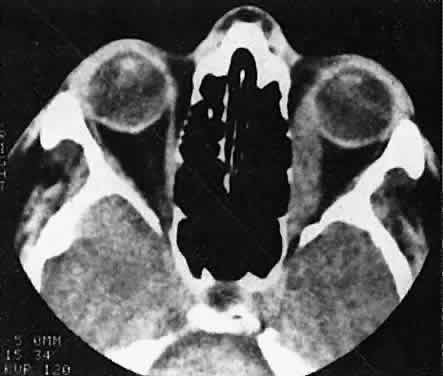

RHABDOMYOSARCOMA Rhabdomyosarcoma is the most common soft-tissue sarcoma in patients younger than 15 years of age and the most common primary orbital malignancy in childhood. These facts should not imply its frequent occurrence. Including all body sites, the annual incidence of childhood rhabdomyosarcoma in the United States is approximately 225 cases.2 The orbit is the site of origin in 5% to 25% of cases.3,4 However, site distribution varies with age. In children 5 to 9 years of age, for example, approximately 40% of primary rhabdomyosarcomas involve the orbit or eyelid.2 Although relatively rare, the tumor has a devastating natural history and demands a high index of suspicion in all cases of pediatric proptosis. Orbital rhabdomyosarcomas are slightly more common in females, with a 0.79 to 1 male-to-female ratio.2 The average age of presentation is 7.8 years, but the tumor may be present at birth and has been reported in patients as old as 78 years.5 A positive family history and associated anomalies have at times been identified, but these are exceptions rather than the rule. Classically, orbital rhabdomyosarcoma presents in an abrupt manner, with rapid progression of proptosis over days to weeks. A somewhat more indolent course does not exclude the diagnosis, however. Vigilance also should be exercised when rapidly expanding eyelid lesions are encountered. Rhabdomyosarcoma may present as ptosis or an eyelid mass rather than with proptosis.4 An eyelid rhabdomyosarcoma can occur as a congenital lesion.6 Within the orbit, rhabdomyosarcoma occurs most often, but not exclusively, in the superior nasal quadrant, with downward and outward displacement of the globe. CT scans show the topography of the orbital mass (Fig. 1A), as well as the possible extension into adjacent bone, paranasal sinuses, or the intracranial cavity. The circumscription that may be noted on CT is relative, because the lesion is not encapsulated and microscopically infiltrates normal tissue. Echography shows internal echoes of low-to-medium amplitude. Because the cellular tumor absorbs acoustic energy, the amplitude of the spikes falls off somewhat through the lesion (see Fig. 1B and C). MRI can help define the tumor's relationship to extraocular muscles (Fig. 2). The clinical diagnosis must be confirmed by biopsy. Because of the risk of seeding the biopsy tract, a transcranial approach should be avoided. If possible, the periosteum should not be violated because it presents a relative barrier to tumor invasion. Depending on its location, the lesion should be approached transconjunctivally or with an eyelid crease incision/transseptal dissection. The surgeon must balance the benefit of complete gross tumor resection with the risks of functional impairment and tumor dissemination that may accompany that effort. Tissue samples should be fixed in formaldehyde solution and glutaraldehyde for light and electron microscopic study. In addition, the value of immunohistochemical differentiation has been established for some time, and the potential uses of molecular genetic studies are rapidly emerging. Consequently, the procurement of fresh or frozen tissue, or both, has been given the highest priority by the Biopathology Discipline within the Intergroup Rhabdomyosarcoma Study Group (IRSG).2 These techniques can facilitate the diagnosis of poorly differentiated tumors, and they may refine diagnostic and prognostic classifications, identify candidate genes, and contribute to potential gene therapies. Since the inception of IRSG-I in 1972, the multicenter collaboration has enrolled the overwhelming majority of patients diagnosed with rhabdomyosarcoma in the United States and has contributed significantly to enhanced patient survival. Patients with orbital tumors had a 96% versus 83% failure-free survival in IRSG-IV compared with those in the IRSG-III.2 As of the year 2000, with the IRSG-V study underway, the overall (all primary sites) 5-year survival of children and adolescents with nonmetastatic and metastatic tumors was approaching 80%. This progress reflects advances in diagnostic imaging and multimodal treatment, including chemotherapy (e.g., agents, combinations, timing), radiation therapy (e.g., doses, fractionation, timing), and surgery (e.g., diagnostic biopsy, local staging, salvage procedures). Therapeutic protocols have evolved over the past 30 years, but they also have not been uniform at any given point in time. Rather, they have been tailored to the patient's level of risk, as determined by multiple prognostic factors (Table 3). The concept of “risk-appropriate therapy”7 recognizes, for example, that a 6-year-old child with an embryonal rhabdomyosarcoma confined to the orbit might do well with a relatively simple chemotherapy protocol, avoiding the late adverse effects of high-dose radiation. Conversely, an 18-year-old patient with an alveolar rhabdomyosarcoma arising in the retroperitoneum, with metastases at presentation, needs aggressive, complex chemotherapy and radiation, and may still do poorly. Prognostic factors considered by the multidisciplinary team include the presence of gross or microscopic residual tumor, and this determination currently is being redefined with molecular techniques that may show residual disease even without microscopic evidence2; whether tumor is confined to the anatomic site of origin or invades surrounding tissues; tumor size, with 5 cm considered a breakpoint; regional lymph node involvement; and distant metastasis. Body site plays a role, and the orbit is relatively favored. The age of the patient at diagnosis is a strong independent predictor of outcome.7 The current pathologic classification for childhood rhabdomyosarcomas by prognosis2 is as follows: